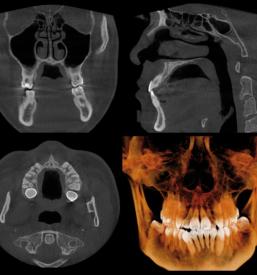

Svojim pacientom nudimo dober RTG zob v Ljubljani, center, kjer se nahaja naša ordinacija. Nudimo vam varno in natančno slikanje zob, ki je odločilnega pomena za nadaljnjo zdravljenje in zobozdravstveno obravnavo.

Pri svojem delu uporabljamo le najboljšo opremo, ki zagotavlja, da je RTG zob, ki ga opravljamo v Ljubljani, center, povsem varen, učinkovit, rezultati pa hitri in nazorni.

Rezultate, ki jih prinaša naš dober RTG zob v Ljubljani interpretirajo strokovnjaki in na podlagi slike določijo diagnozo in nadaljnjo zdravljenje, ki je potrebno za doseganje optimalnega stanja.